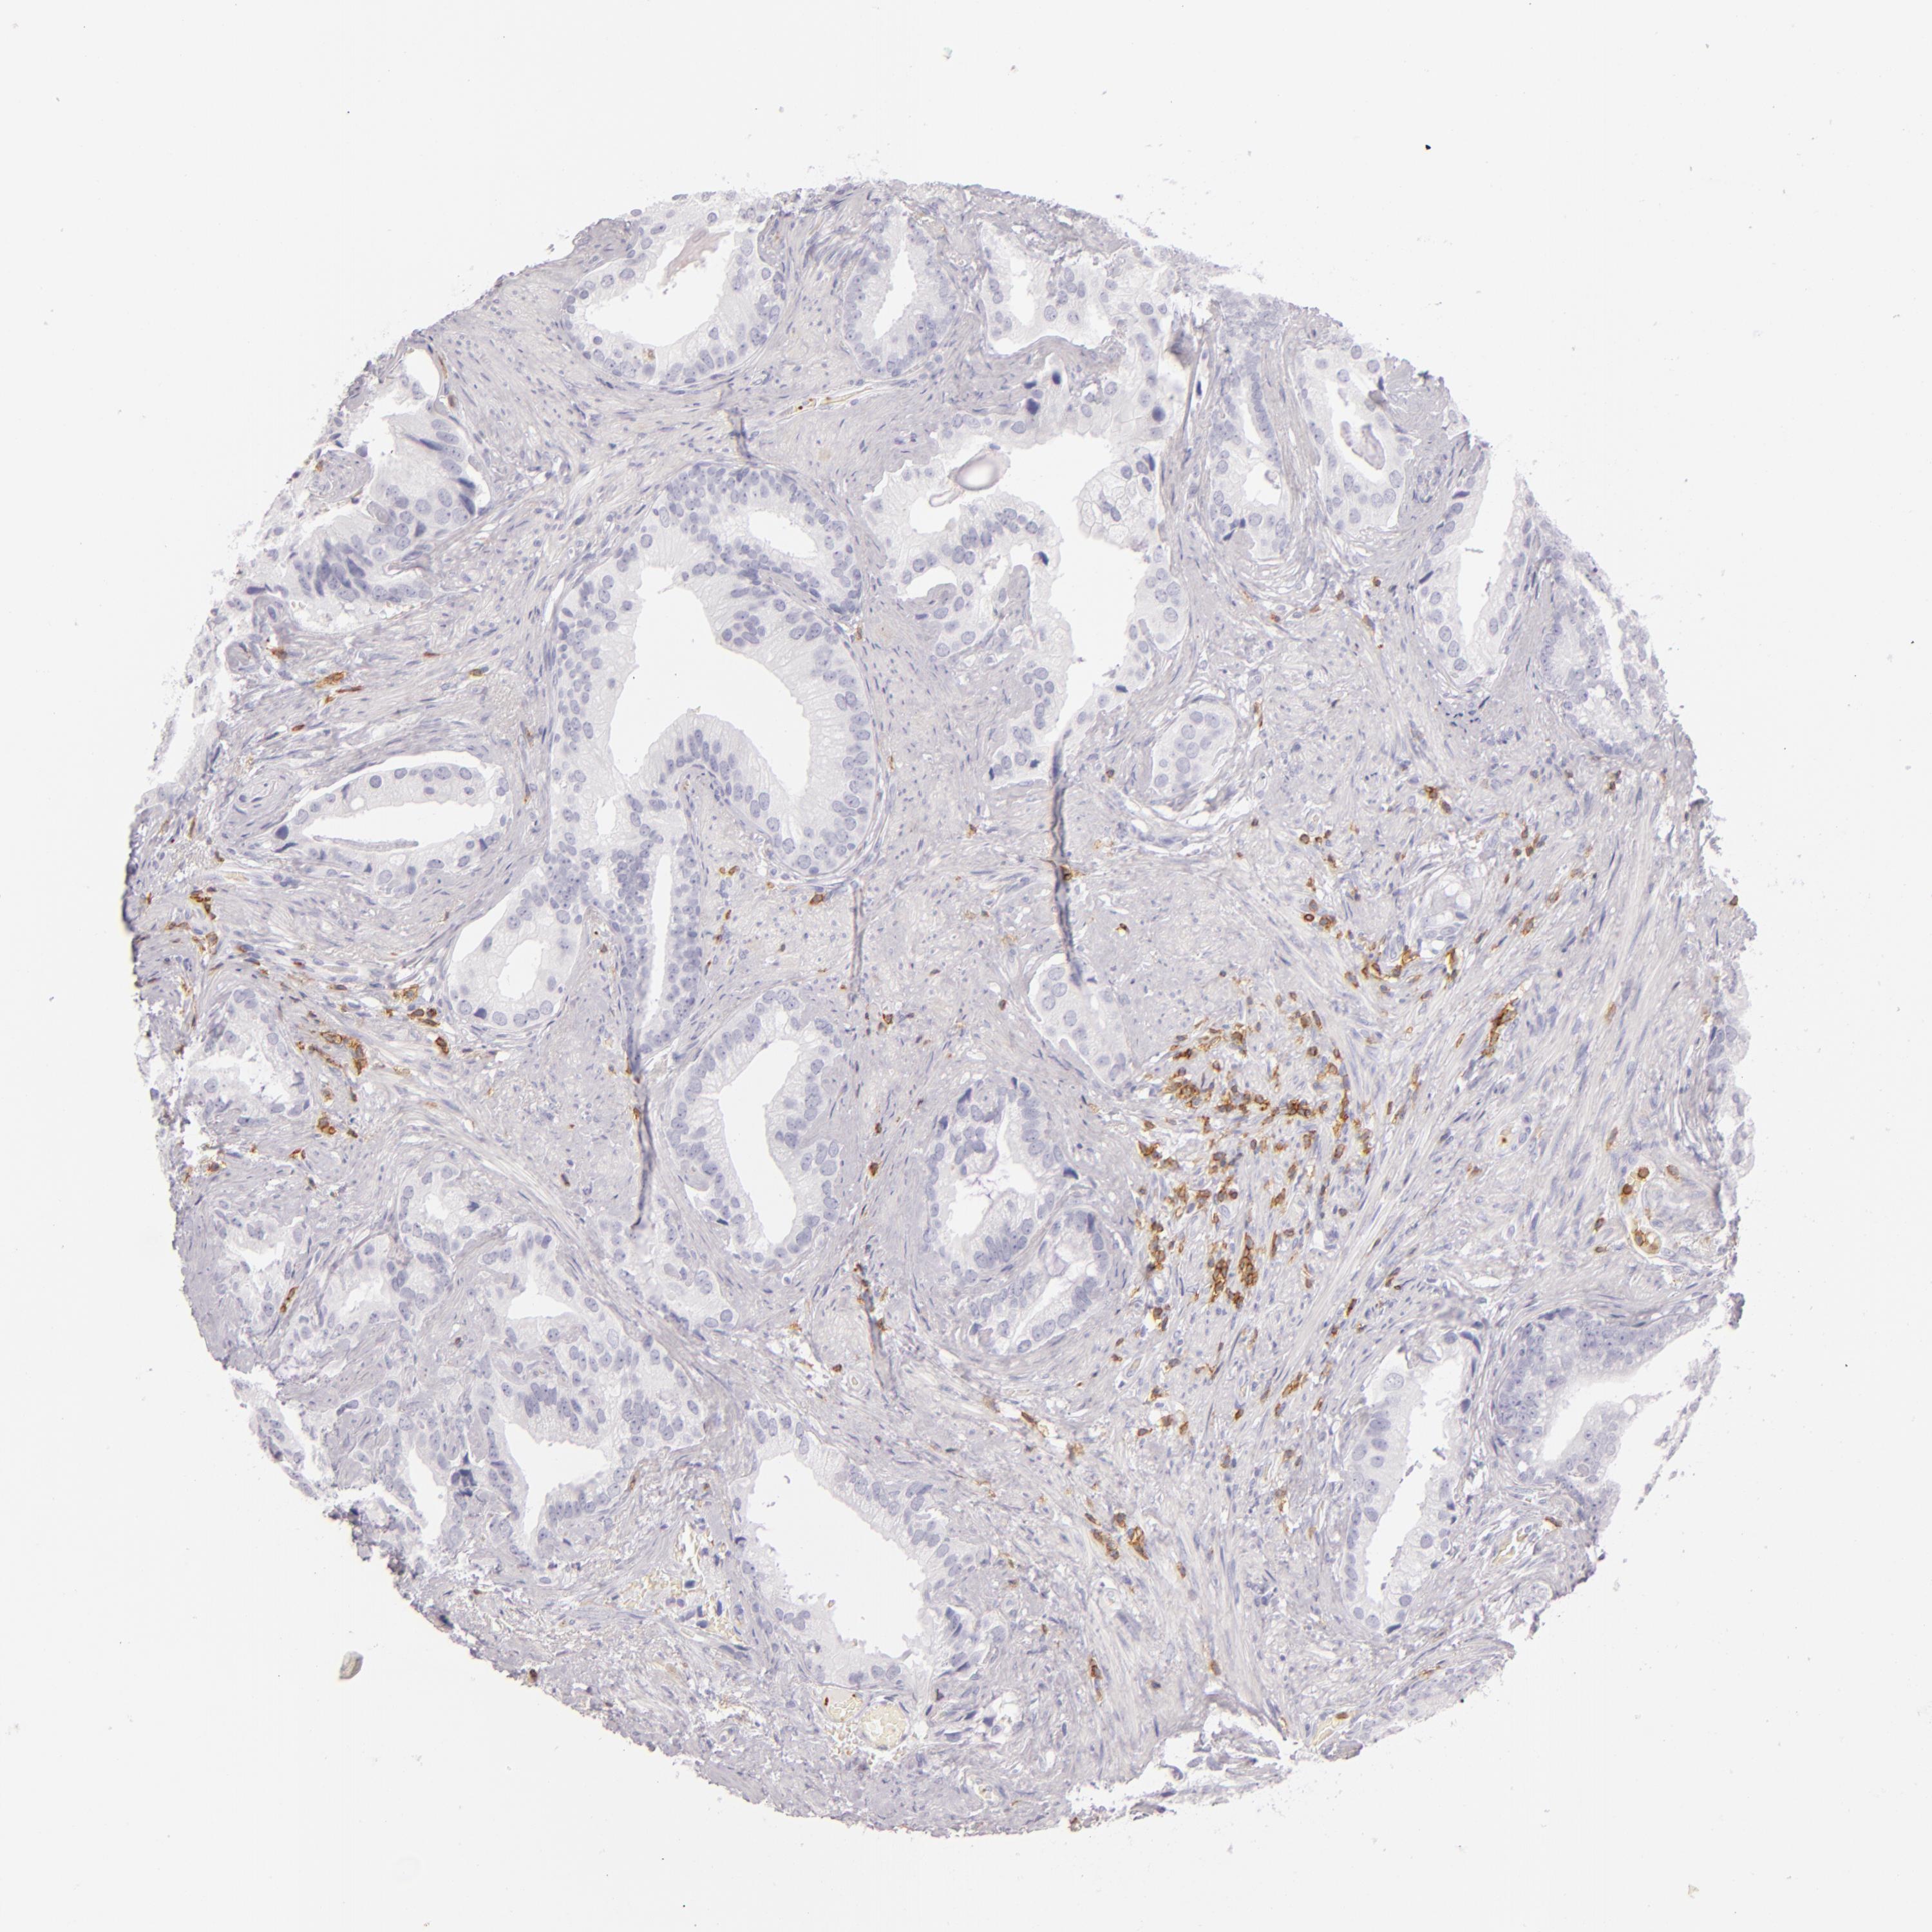

PROSTATE CANCER - Protein expressioni

A mouse-over function shows sample information and annotation data. Click on an image to view it in a full screen mode. Samples can be filtered based on level of antibody staining by selecting one or several of the following categories: high, medium, low and not detected. The assay and annotation is described here.

Note that samples used for immunohistochemistry by the Human Protein Atlas do not correspond to samples in the TCGA dataset.

Antibody stainingi

Antibody staining in the annotated cell types in the current human tissue is reported as not detected, low, medium, or high, based on conventional immunohistochemistry profiling in selected tissues. This score is based on the combination of the staining intensity and fraction of stained cells.

Each image is clickable and will lead to virtual microscopy that enables deeper exploration of all samples and also displays staining intensity scores, fraction scores and subcellular localization as well as patient and tissue information for each sample.

Antibody HPA011157

Antibody CAB002223

Antibody CAB012978

Antibody CAB079960

Staining

High

Medium

Low

Not detected

Intensity

Strong

Moderate

Weak

Negative

Quantity

>75%

75%-25%

<25%

None

Location

Nuclear

Cytoplasmic/membranous

Cytoplasmic/membranous,nuclear

Adenocarcinoma, Low grade

Adenocarcinoma, High grade

Adenocarcinoma, Medium grade

Adenocarcinoma, NOS